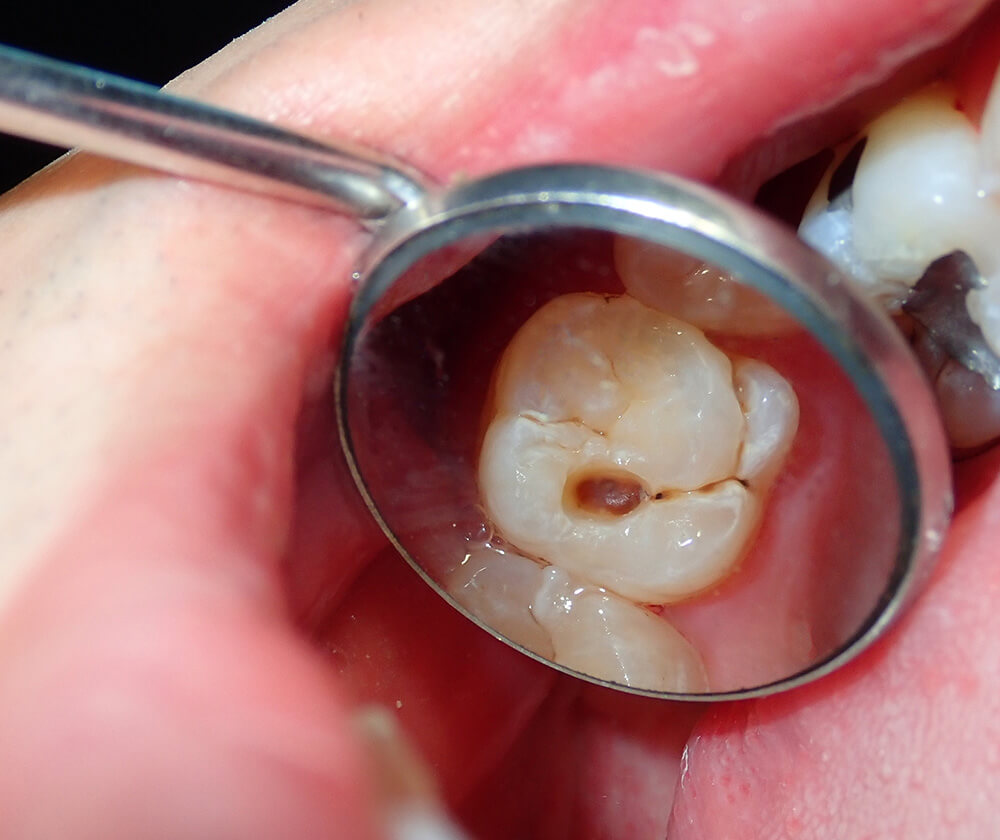

虫歯や歯周病は誰でも治せると思われがちですが、実はそうではありません。原因は「歯ぎしり」による「歯のひび」で、そこから菌が侵入して虫歯になります。当院では、歯ぎしりをコントロールして治療を行っています。